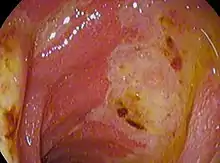

![]() | |

| Deep gastric ulcer | |